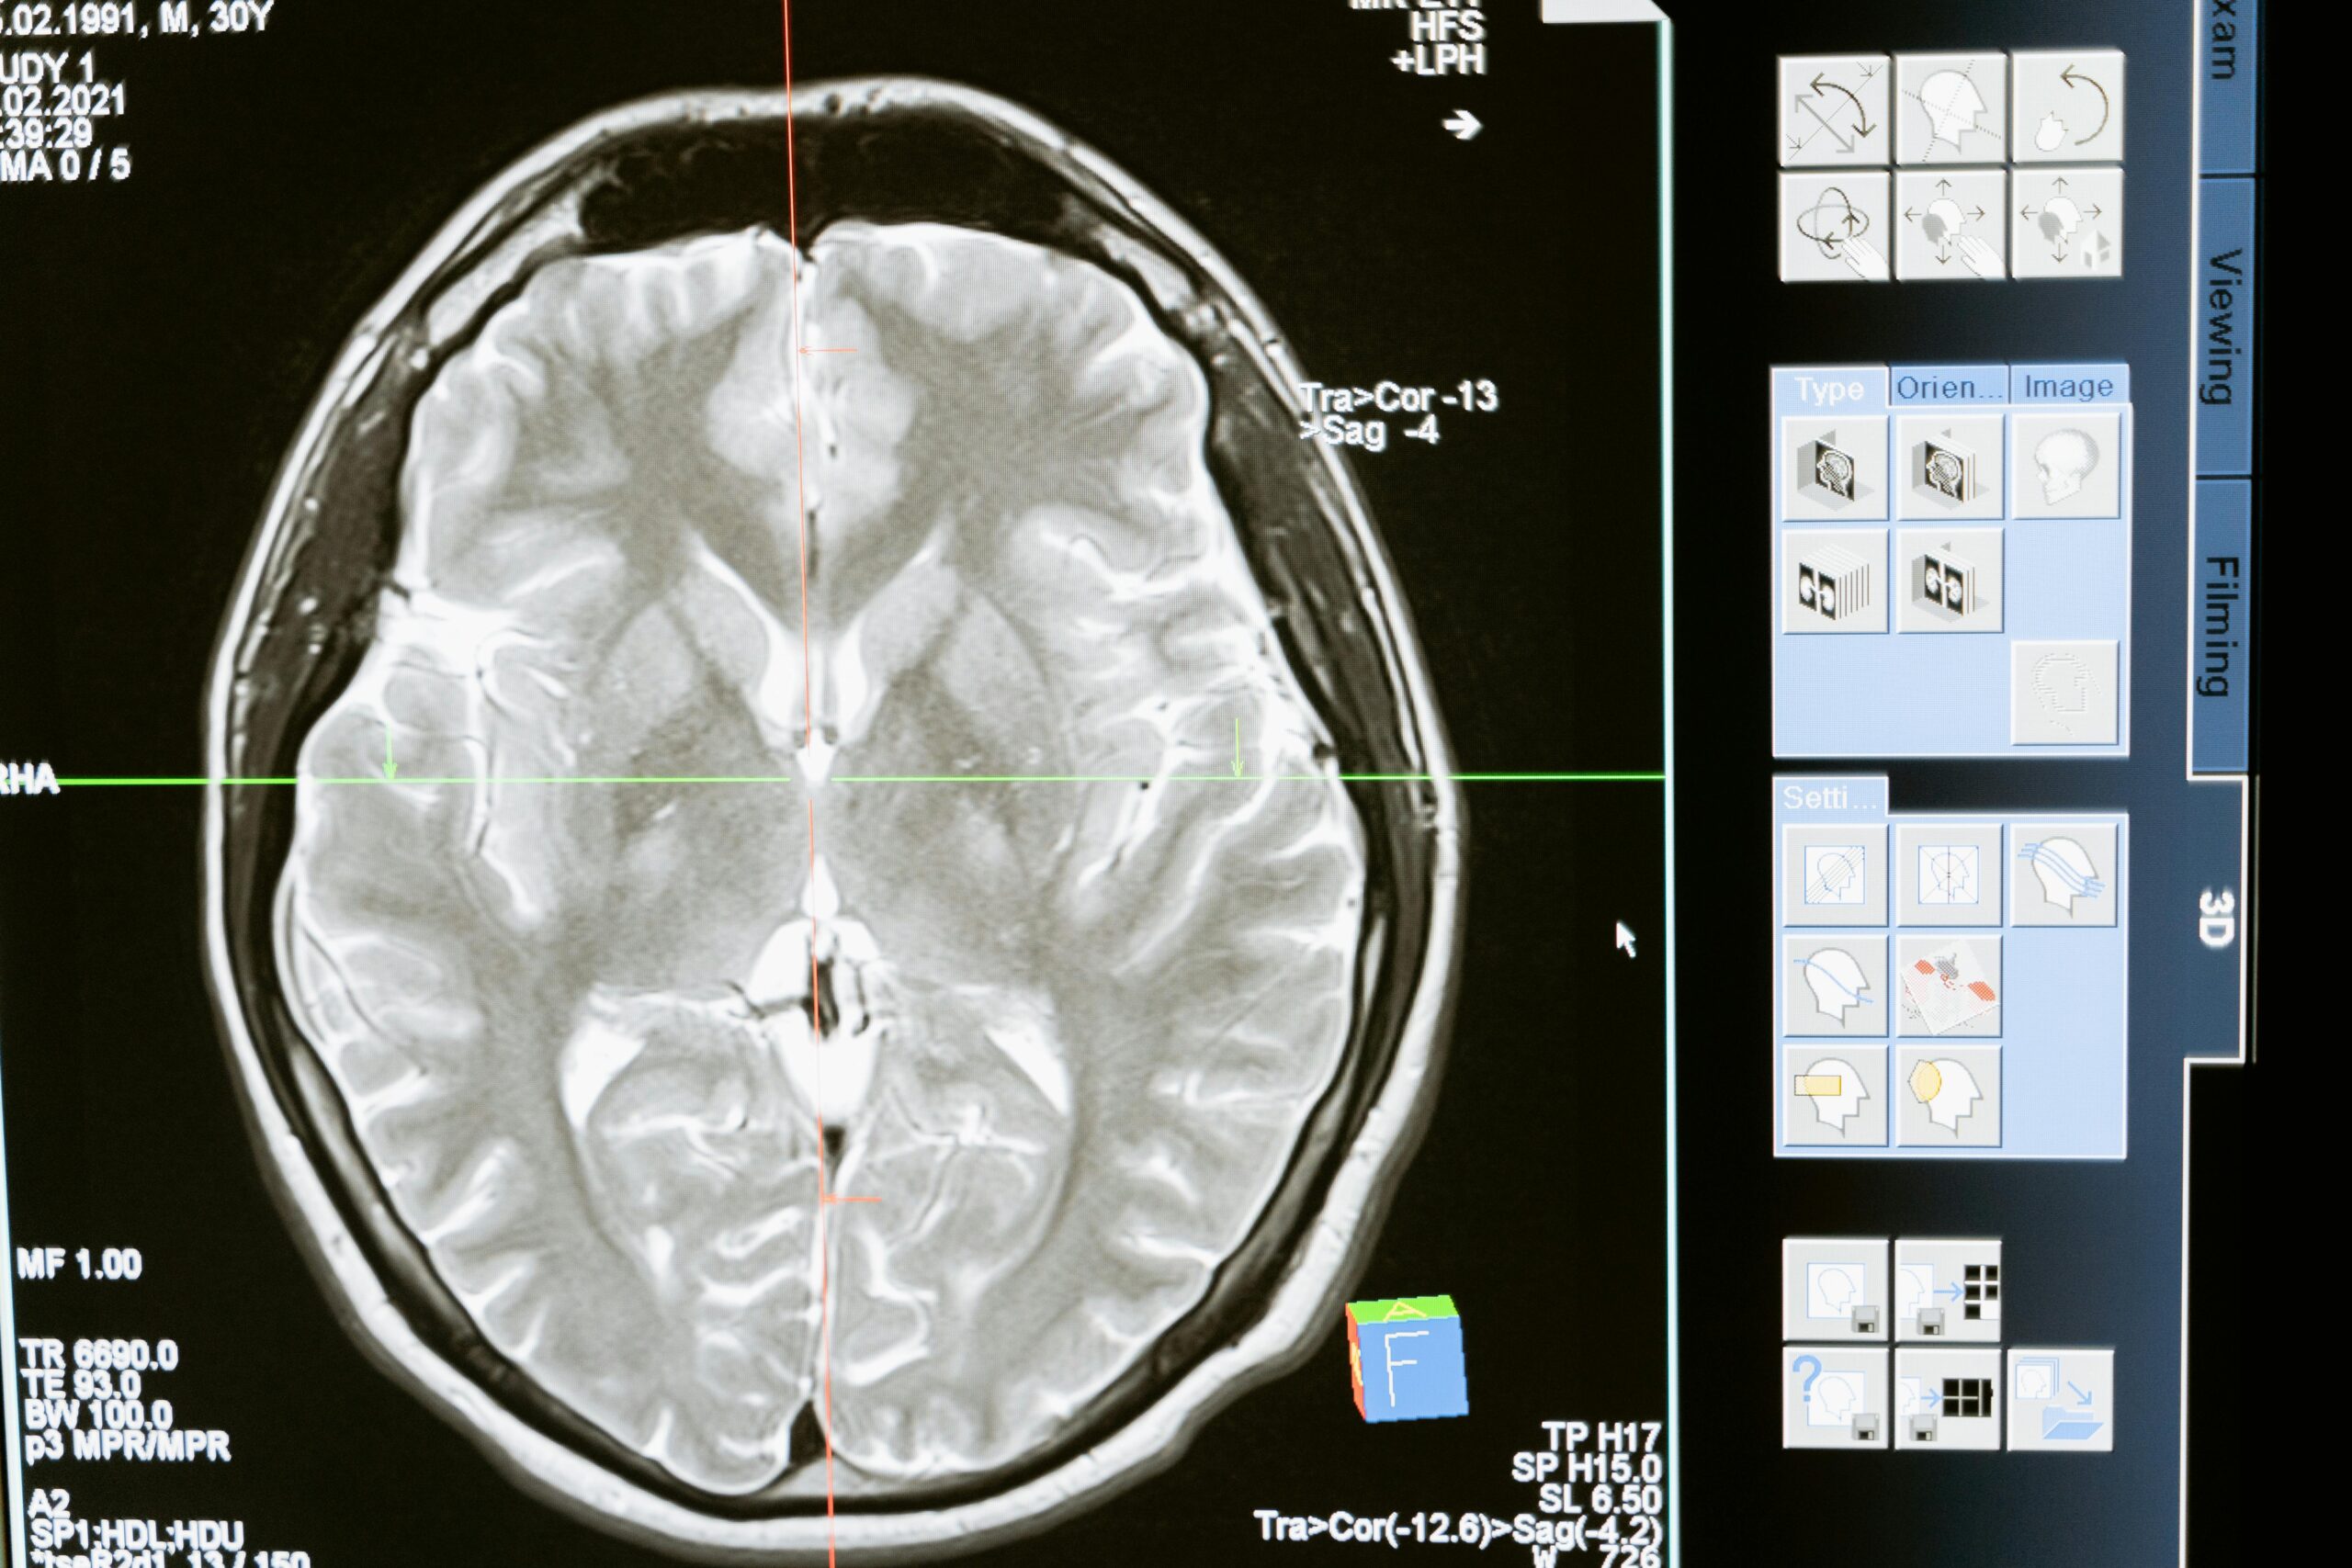

Sometimes we get a glimpse into the world of disease not usually evaluated by cerebral angiography. No doubt, this is a rediscovery of long forgotten facts from pre-cross-sectional era. This 60+ patient came in with mild confusion and amnesia. A CT scan showed hyperdensity in the posterior left hippocamal formation (pink arrows), which was initially interpreted as being in the adjacent perihippocampal cistern, raising the specter of subarachnoid hemorrhage.